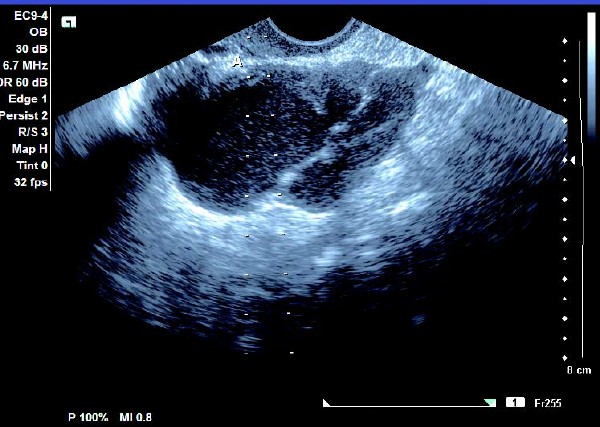

患者,女,35岁。每次月经量少,痛经,近来行经期延长、疼痛加重来院诊治。超声报告显示子宫前倾位,子宫体大小为:5.9cm×5.1cm×4.8cm,形态规则,边界清晰,宫避回声匀称,宫腔线居中,内膜厚度0.6cm,宫内未见异常回声。右侧卵巢内可见大小约5.2 cm×4.9cm的无回声区暗区,壁厚,内壁欠光滑,内见密集细光点,边界清晰。CDFI探测囊壁及囊腔内无血流信号。

超声提示:右侧卵巢巧克力囊肿